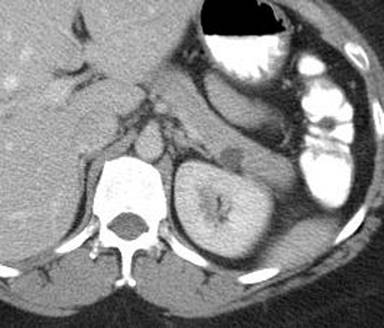

A 42-year-old female was referred for evaluation of an incidental pancreatic tail cyst found on CT (Figure 4). Initial EUS assessment revealed a 17x10 mm anechoic and thinly septated cyst. The FNA aspirate was a thin clear fluid with a CEA level of 9.4 ng/mL. Cytology revealed a few clusters of bland epithelial cells (mucicarmine negative) and debris. Given the possibility that this could still represent a mucinous cystic neoplasm, surveillance EUS was recommended. One year later, EUS revealed a 15x12 mm thinly septated cyst (Figure 5); however, the fluid was slightly viscous, with an elevated CEA level of 9,646 ng/mL. Cytology revealed numerous hemosiderin-laden histiocytes and rare ductal epithelial cells. Given suspicion for mucinous cystic neoplasm, the patient underwent laparoscopic resection, and surgical pathology verified a mucinous cystic neoplasm with low grade dysplasia.

Figure 4. CT scan of a small cyst in the pancreatic tail. (Patient #2). |